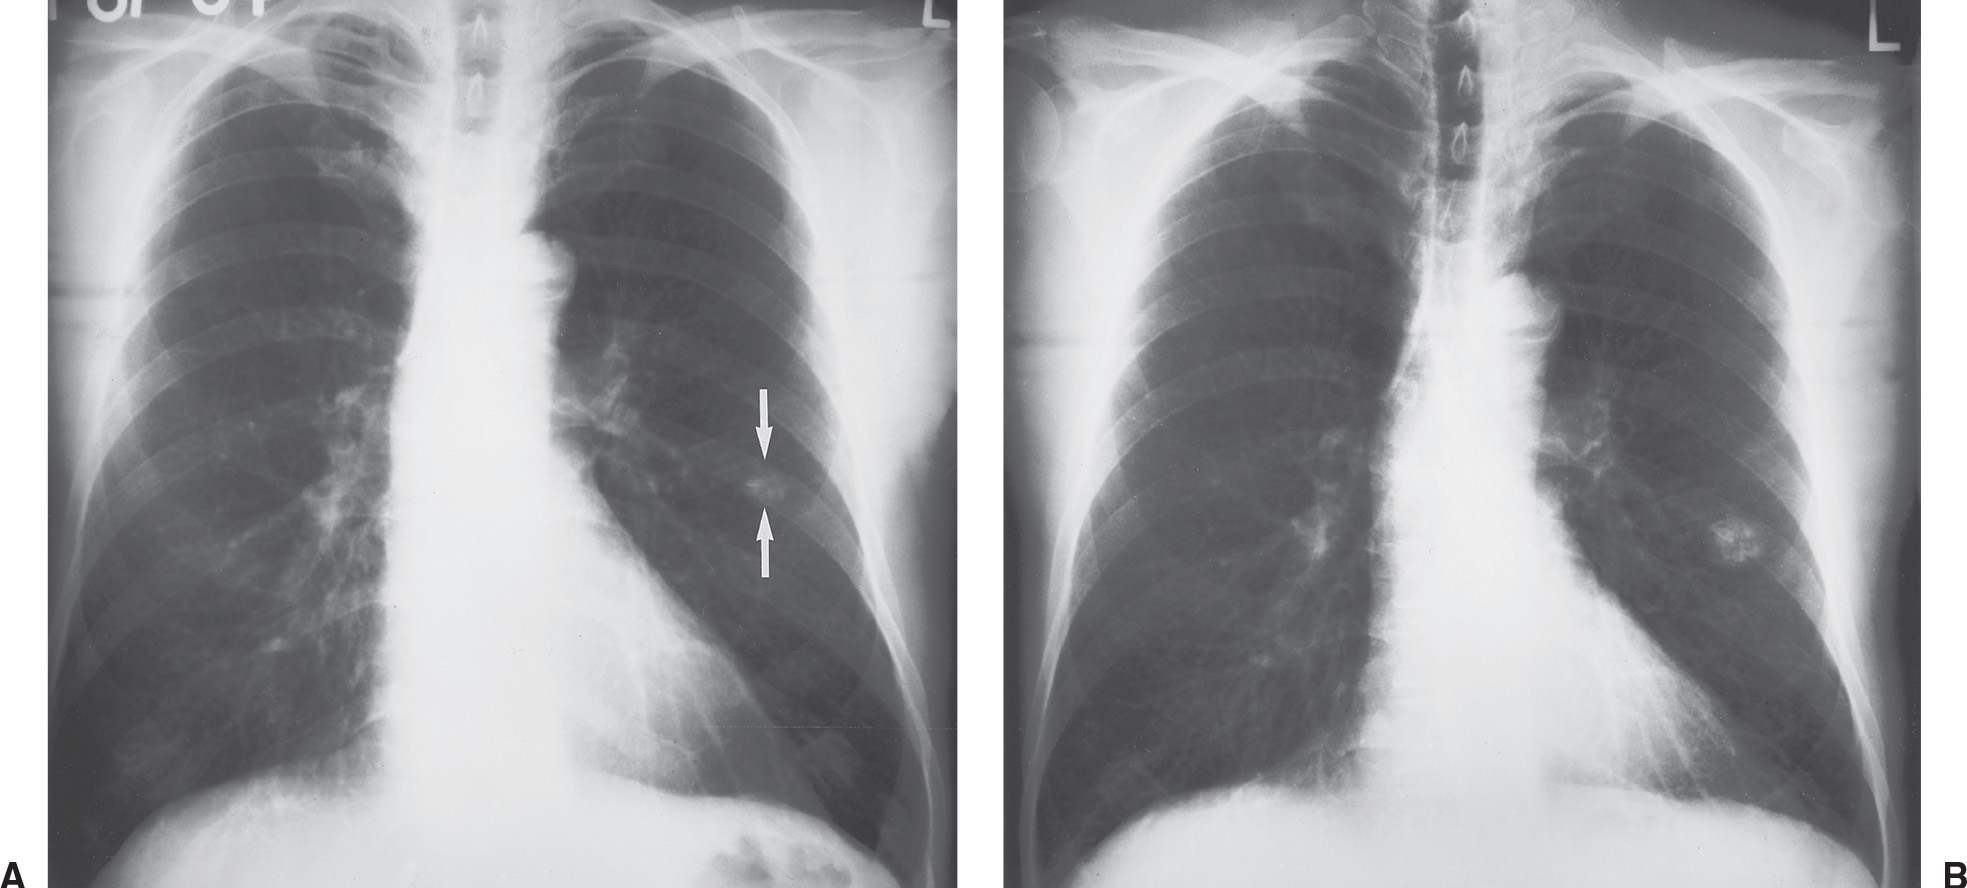

Chest Xrays after 4 months of therapy shows that the lung nodules have Can Lung Nodules Be Seen On Xray They’re very common, and at least 95% aren’t cancerous. In some cases, though, more tests might be required to ensure the. Lung nodules often are discovered. Having multiple lung nodules means you have two or more lesions in your lungs. Common lung nodule causes may include scar tissue,. Nodules are areas that are denser than normal lung tissue and usually. Can Lung Nodules Be Seen On Xray.

Chest Xray showing multiple lung nodules with multifoc Openi Can Lung Nodules Be Seen On Xray Lung nodules often are discovered. Having multiple lung nodules means you have two or more lesions in your lungs. In some cases, though, more tests might be required to ensure the. Multiple lung nodules are also called pulmonary nodules. They’re very common, and at least 95% aren’t cancerous. How are lung nodules detected and evaluated? Lung nodules are small masses. Can Lung Nodules Be Seen On Xray.

Multiple Lung Nodules Undergraduate Diagnostic Imaging Fundamentals Can Lung Nodules Be Seen On Xray Nodules are areas that are denser than normal lung tissue and usually don't cause symptoms. Having multiple lung nodules means you have two or more lesions in your lungs. First, you may be comforted to know that, while lung nodules may be an indicator of lung cancer, benign nodules are common. How are lung nodules detected and evaluated? Multiple lung. Can Lung Nodules Be Seen On Xray.